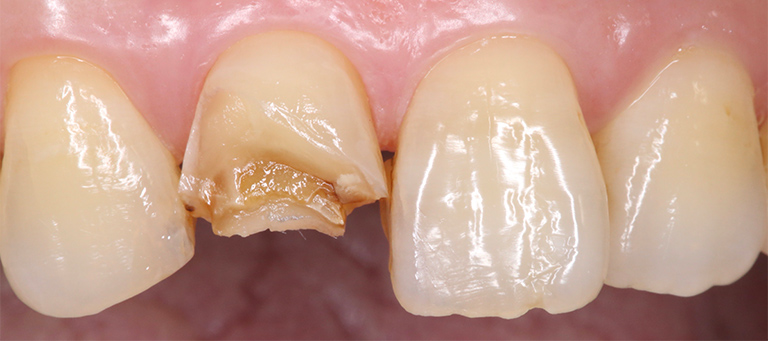

前歯が折れた

- 治療前の状態

- 空隙歯列(すきっぱ)、歯牙形態の不整

- 治療内容

- ホワイトニング・ラミネートベニア

【治療のリスク・注意点】

定期検診で噛み合わせをチェックする必要があり、調整を行うこともあります。噛み合わせの調整に費用はかかりません。メンテナンスが甘い場合、セラミックが欠けたり破損したりすることがあります。

ホワイトニングはほとんどの方が歯を白く明るく変化させることができますが、ごく稀にあまり変化が見られない場合もあります。この方は問題ありませんでした。